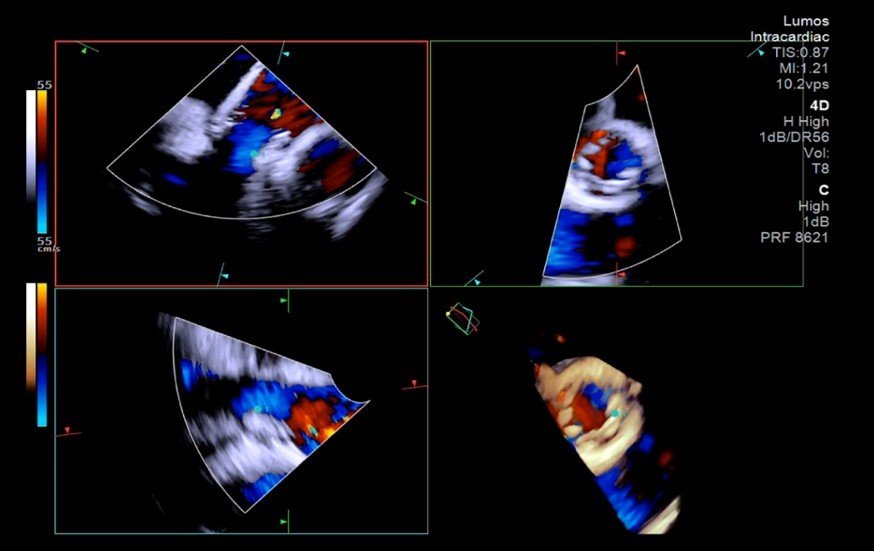

4차원(4D) 심장내 초음파(intracardiac echocardiography, ICE) 영상 이미지 사진제공 |중앙대광명병원

4D 심장내 초음파는 심장 내부의 구조를 실시간으로 정밀하게 보여주는 고해상도 영상 기술이다. 심장내 초음파 분야의 최고 권위자인 임홍의 교수는 “입체적 영상을 실시간으로 활용하면 시술자는 심장과 시술 장치의 구조를 보다 정확하게 파악할 수 있어, 시술의 효율성과 안전성을 최대로 높일 수 있다”며 “특히 정밀한 기술이 요구되는 경피적 대동맥판막 삽입술과 같은 고난도 시술에서 그 활용도가 더욱 기대된다”고 밝혔다